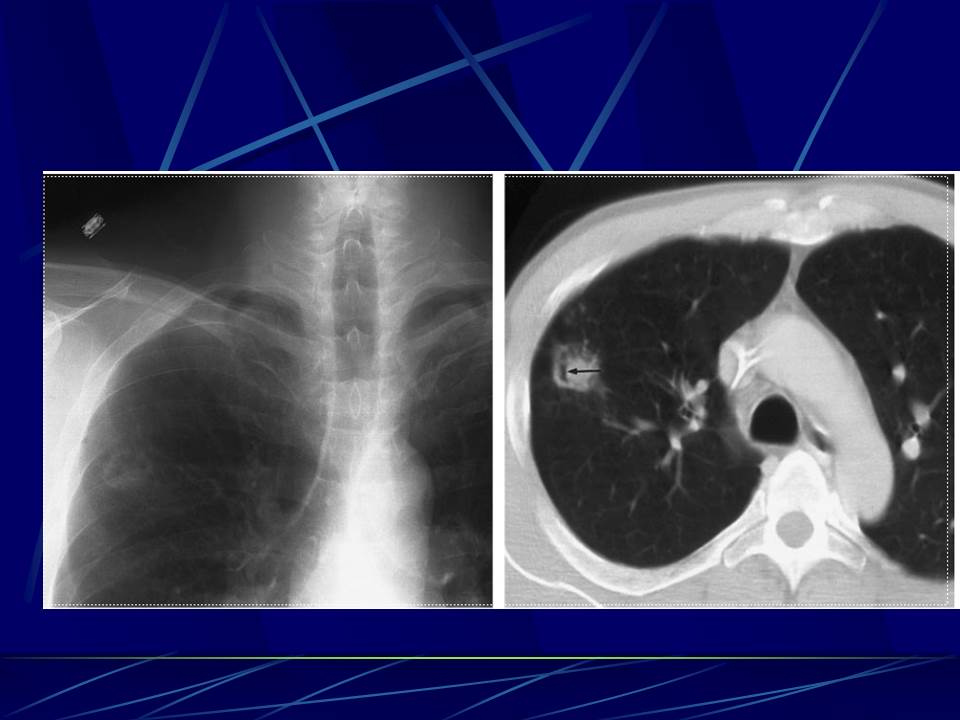

肺部真菌感染影像学分析